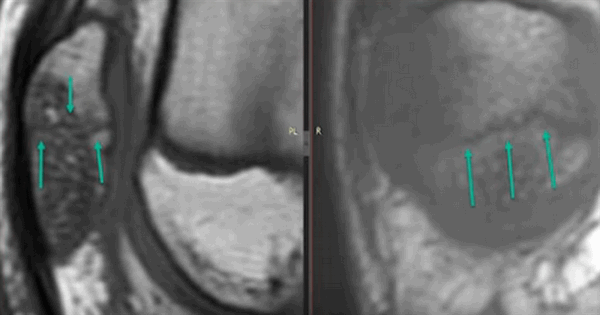

Контузия трабекулярной костной ткани (указана стрелками) без нарушения целостности кости на МРТ

Субхондральный перелом латерального мыщелка на МРТ (указан стрелками)